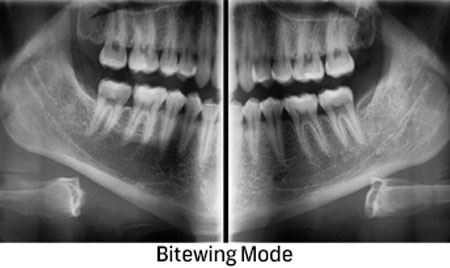

For an exact diagnosis and a target-oriented treatment it is necessary to look inside the tooth. EDG offers wide range of 2D and 3D CBCT Digital Radiography.

We use the newest technology to enable a precise treatment for our patients through imaging methods.